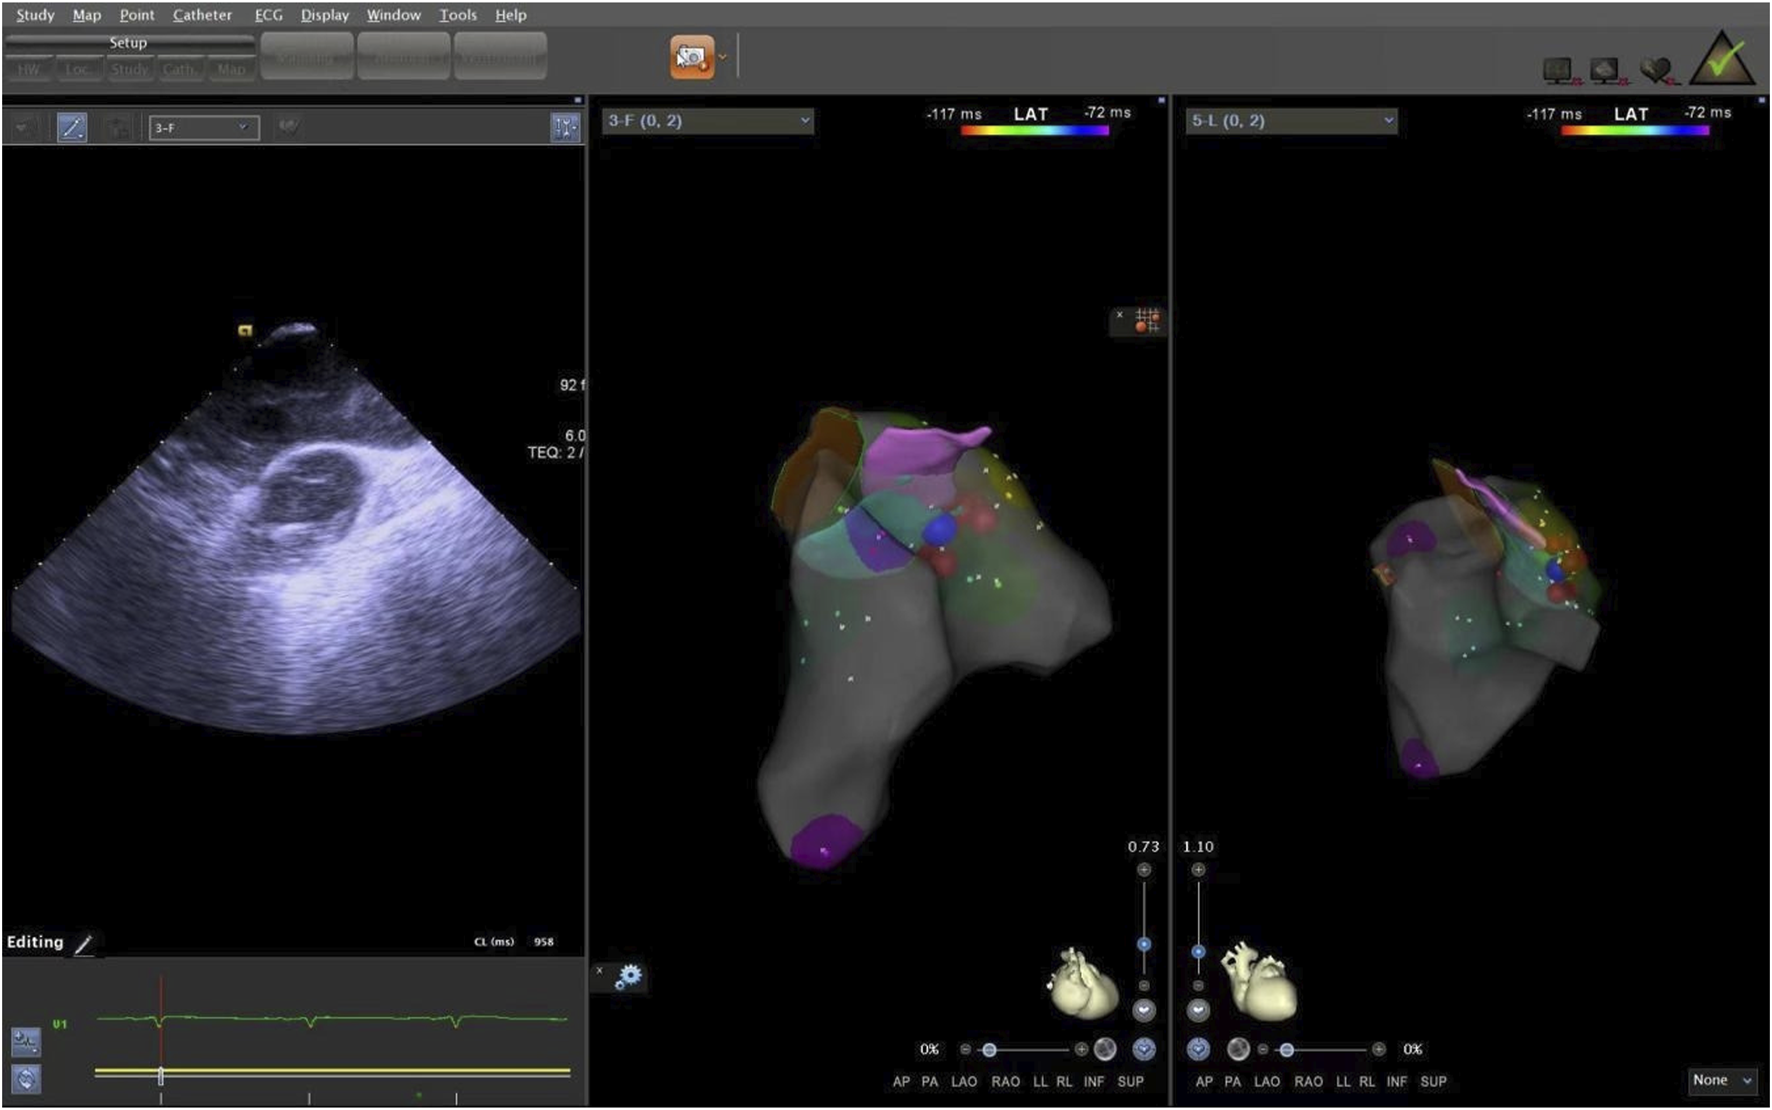

The supra-pulmonary sinus position is located above the pulmonary sinus junction plane. The infra-pulmonary sinus position includes locations at or below the pulmonary sinus junction plane, extending within 10 mm from the sinus floor (Acosta et al., 2015). After identifying the ablation target, radiofrequency ablation was performed with preset parameters of 43°C and 30W. The effectiveness of energy delivery (Dragasis et al., 2022) was validated by the disappearance of PVCs during ablation, and the duration of effective ablation was documented. The success criteria were defined as follows: 1) Complete elimination of PVCs on electroanatomic mapping; 2) Absence of preoperative-type premature contractions for 20–30 min after isoproterenol provocation. During the procedure, the CARTO3 three-dimensional anatomical mapping system and ICE were used to record the time, amplitude, and duration of bipolar potentials at the earliest activation site, in relation to the onset of the QRS complex on the surface electrocardiogram. We measured the distance from the effective ablation sites to the pulmonary artery sinus floor. After the procedure, we used ICE again to locate the ablation points, confirming the precise locations of the ablation targets (Figures 7, 8).

Figure 7. The ablation target of junction of LPC and APC. LPC, Left pulmonary cusp; APC, Anterior pulmonary cusp.